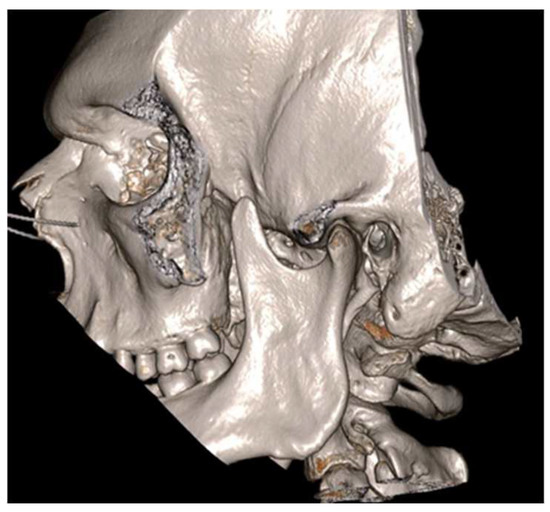

Figure 2.

Cinematic 3D reconstruction (Mimics, Materialise NV, Leuven, Belgium) showing the pseudojoint established between the altered right CPM and the inner aspect of zygomatic bone.

Figure 11.

3-dimensional dynamic reconstruction showing the bilateral pseudojoint determining a bilateral JD.